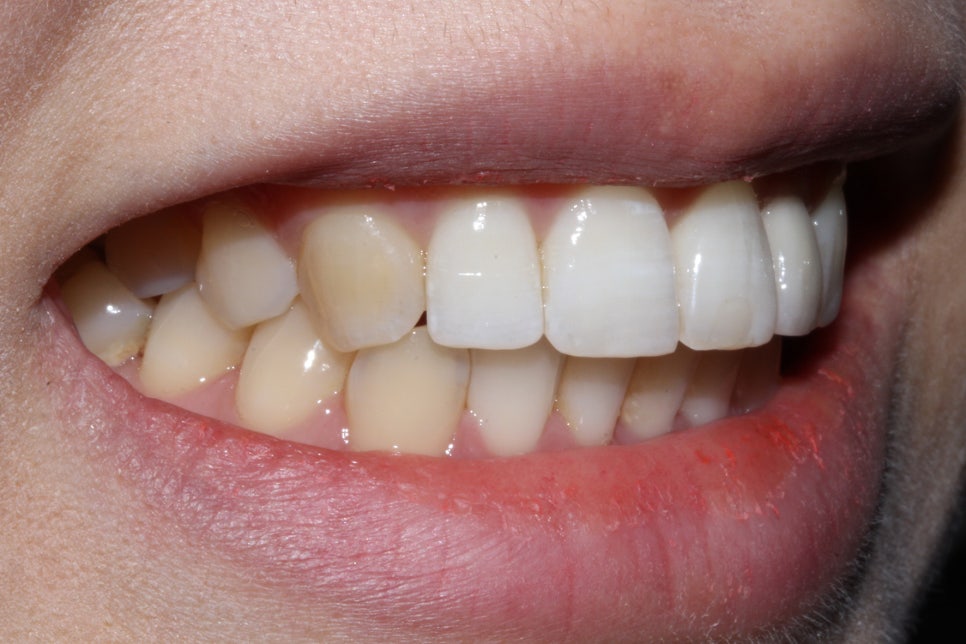

신논현역치과 뻐드렁니 case의 구외 사진입니다.

교정 전 입술과 입 주변의 형태를 보면

좌우의 대칭이 잘 맞지 않고 돌출된 느낌이 있는 모습인데요,

상악 좌측 측절치가 왜소치 증상이 있고

앞니(중절치)가 주변 치열보다 뻐드러져 있어

입술을 다물었을 때도 돌출감이 느껴지는 모습입니다.

특히 스마일라인의 치아가 측절치 및 탈회가 있는

중절치로 인해 심미성이 떨어져 보이기 때문에

교정 및 보철치료를 통해 이를 보완하려고 하는데요,

비발치 교정 후 입술의 모습입니다.

교정 전 치아의 뻐드러짐과 돌출 증상으로 인해

입술이 튀어나와 보이고 돌출감이 느껴지는 모습이었는데요,

교정치료 후 입술의 좌우 대칭이 균형있게 바뀌었으며

상대적으로 두꺼워보이던 아랫입술도 균일하게

교정된 것을 확인할 수 있습니다.